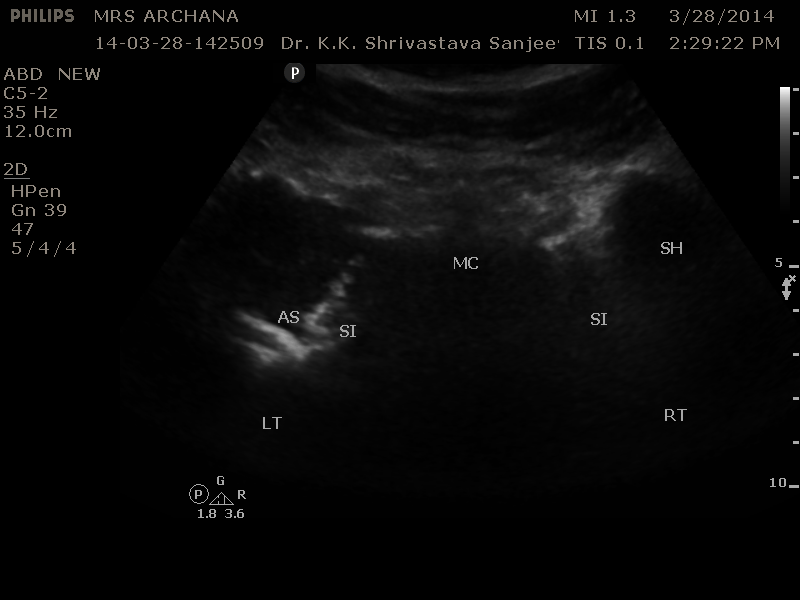

The scan transducer was changed to curvilinear Multifrequency probe ( 5-3 Mhz).

Left S.I. Joint shows altered configuration with underlying cortical destruction of bony land marks as compared to the right side.

Targeted view of the left S.I. Joint is showing distended capsule with homogenous fluid collection associated with cortical erosion of the sacral and ileum articular surfaces.

Provisional diagnosis of cold abscess secondary to Koch’s Left S.I. Joint was made .

A confirmation by way of FNA for tissue diagnosis was instituted at the same sitting under USG guidance .